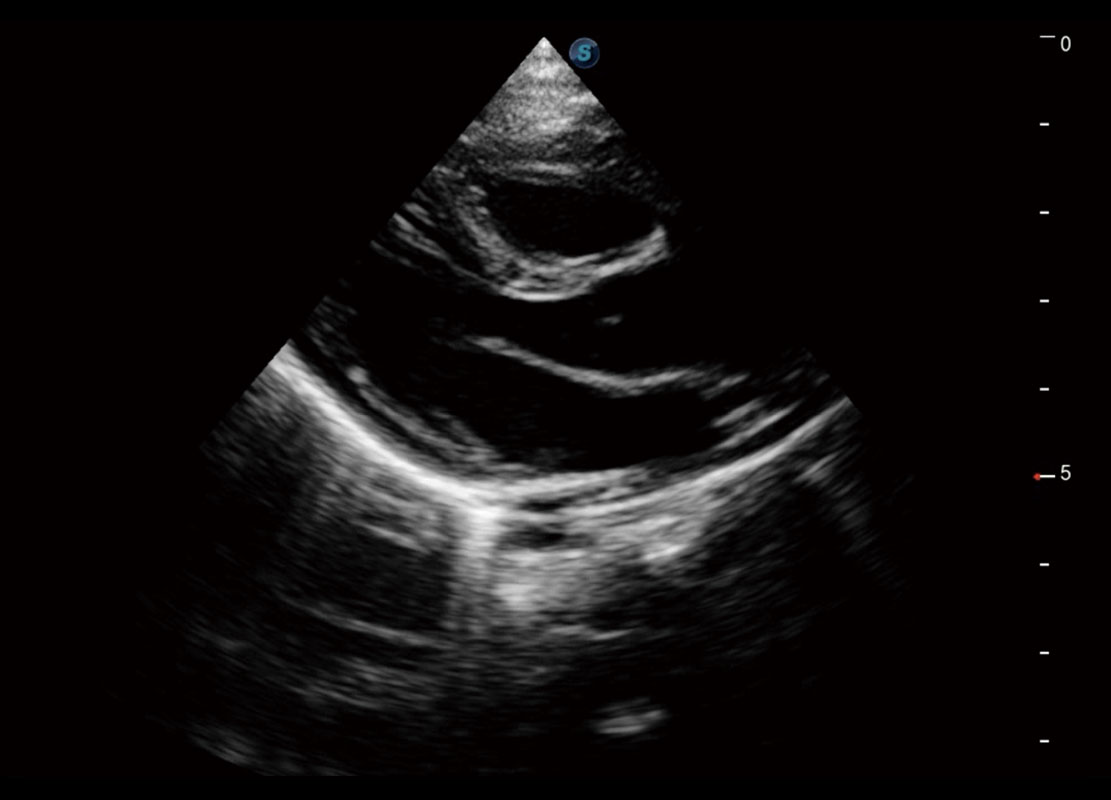

P60搭载一系列胎儿心脏成像技术,实现精细的胎儿心脏评估。

四腔切面

胎心容积成像